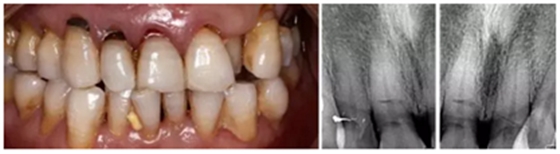

1.臨床病例:患者,男,年齡73歲,不慎摔倒至右上頜側(cè)切牙、左右上頜中切牙外傷根折,X線檢查:12、11、21折裂線達(dá)牙頸部以下。CBCT檢查:12、11、21折裂線呈水平狀,達(dá)牙頸部以下。

1.png

2.診斷:左上頜側(cè)切牙、左右上頜中切牙根折